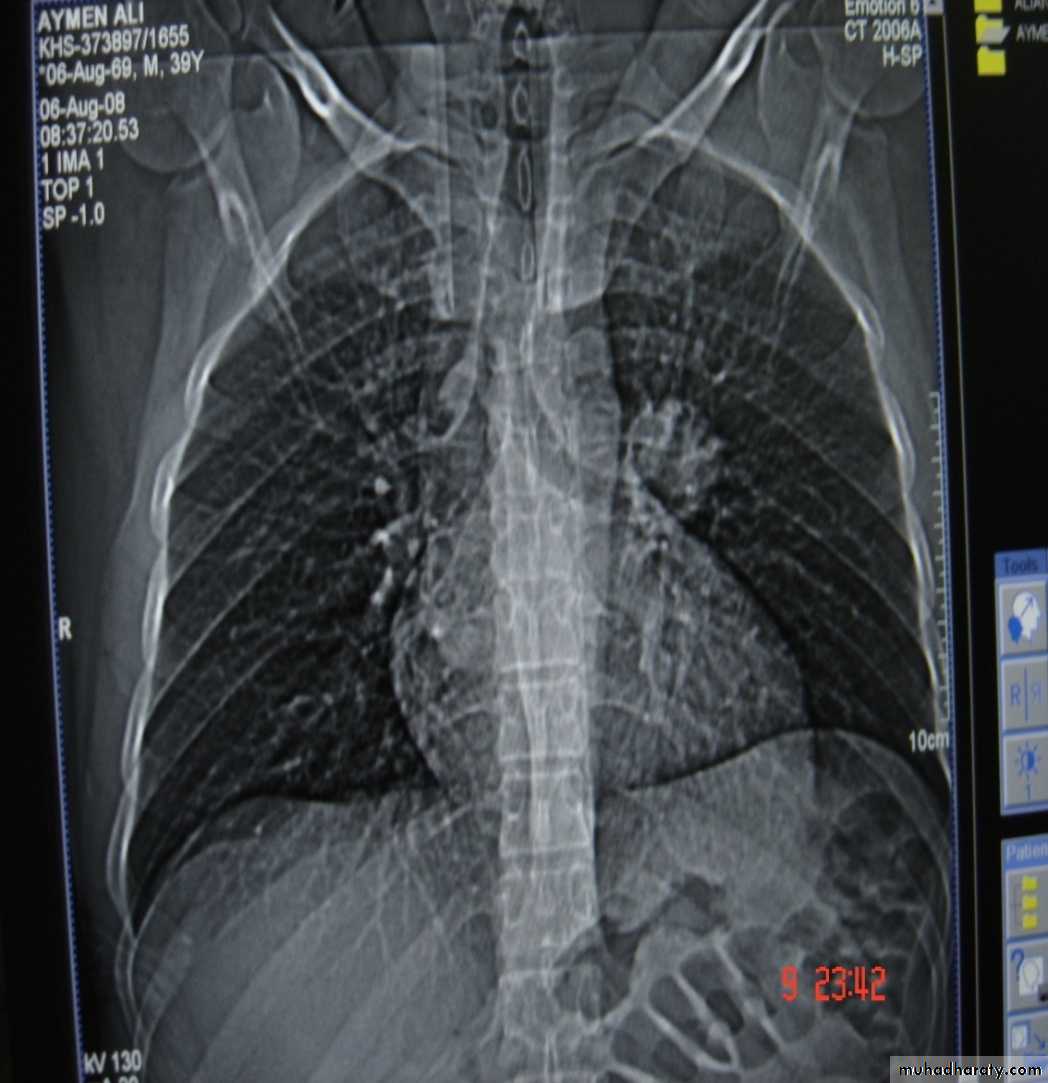

• Pathology :-A-Central type is the commonest (75%).It arises in one of the main bronchi or their primary division leading to bronchial obstruction with secondary changes in the lung such as atelectasis .B-Peripheral type (25%) arises from the smaller bronchi and remains symptom less for long time .

Histologically Squamous cell Ca (SCC) 60% , smoker , centrally located ,metastasizes to mediastinal & supraclavicular LN . Adenocarcinoma (15% ) , located peripherally , more in women .Tends to metastasizes to the liver , brain ,bone & adrenals in addition to the LN Undifferentiated carcinoma (oat) cell carcinoma and large cell carcino(20-30%) which includes small cell Ca Alveolar cell carcinoma , located peripherally ,metastasizes to the liver and adrenalsRecent classification..Non small & small cell carcinoma

• Chest X-ray ,CT chest ..

• TNM classification for staging